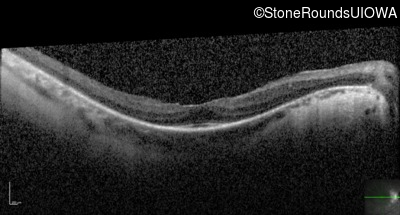

Optical Coherence Tomography - Right - 20/50 +1

Exemplar / OCT Stack

OCT Stack